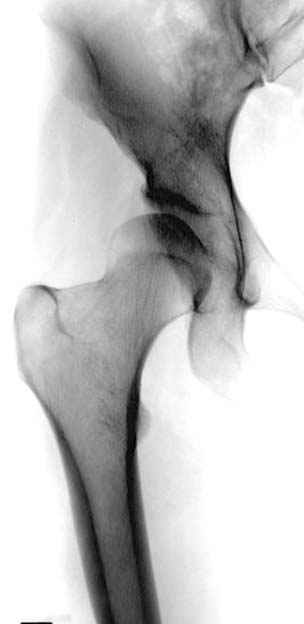

Рис.1 Трехмерная модель тазобедренного сустава с аналогом связки головки бедра. Заметно, что из торца головки выходит капроновый шнур, который с одной стороны прикрепляется к ножке бедренной части модели, а другой его конец, проходя через головку и прикрепляется к вертлужной части модели. Динамометр оказывается не нагруженным, так как аналог связки головки бедра замыкает подвижный узел модели во фронтальной плоскости.

Рис.2 Та же трехмерная модель тазобедренного сустава без аналога связки головки бедра. Пружина динамометра удерживает тазовую часть модели от опрокидывания, поддерживая стабильность так же, как отводящие мышцы обеспечивают ее в отсутствии связки головки бедра.